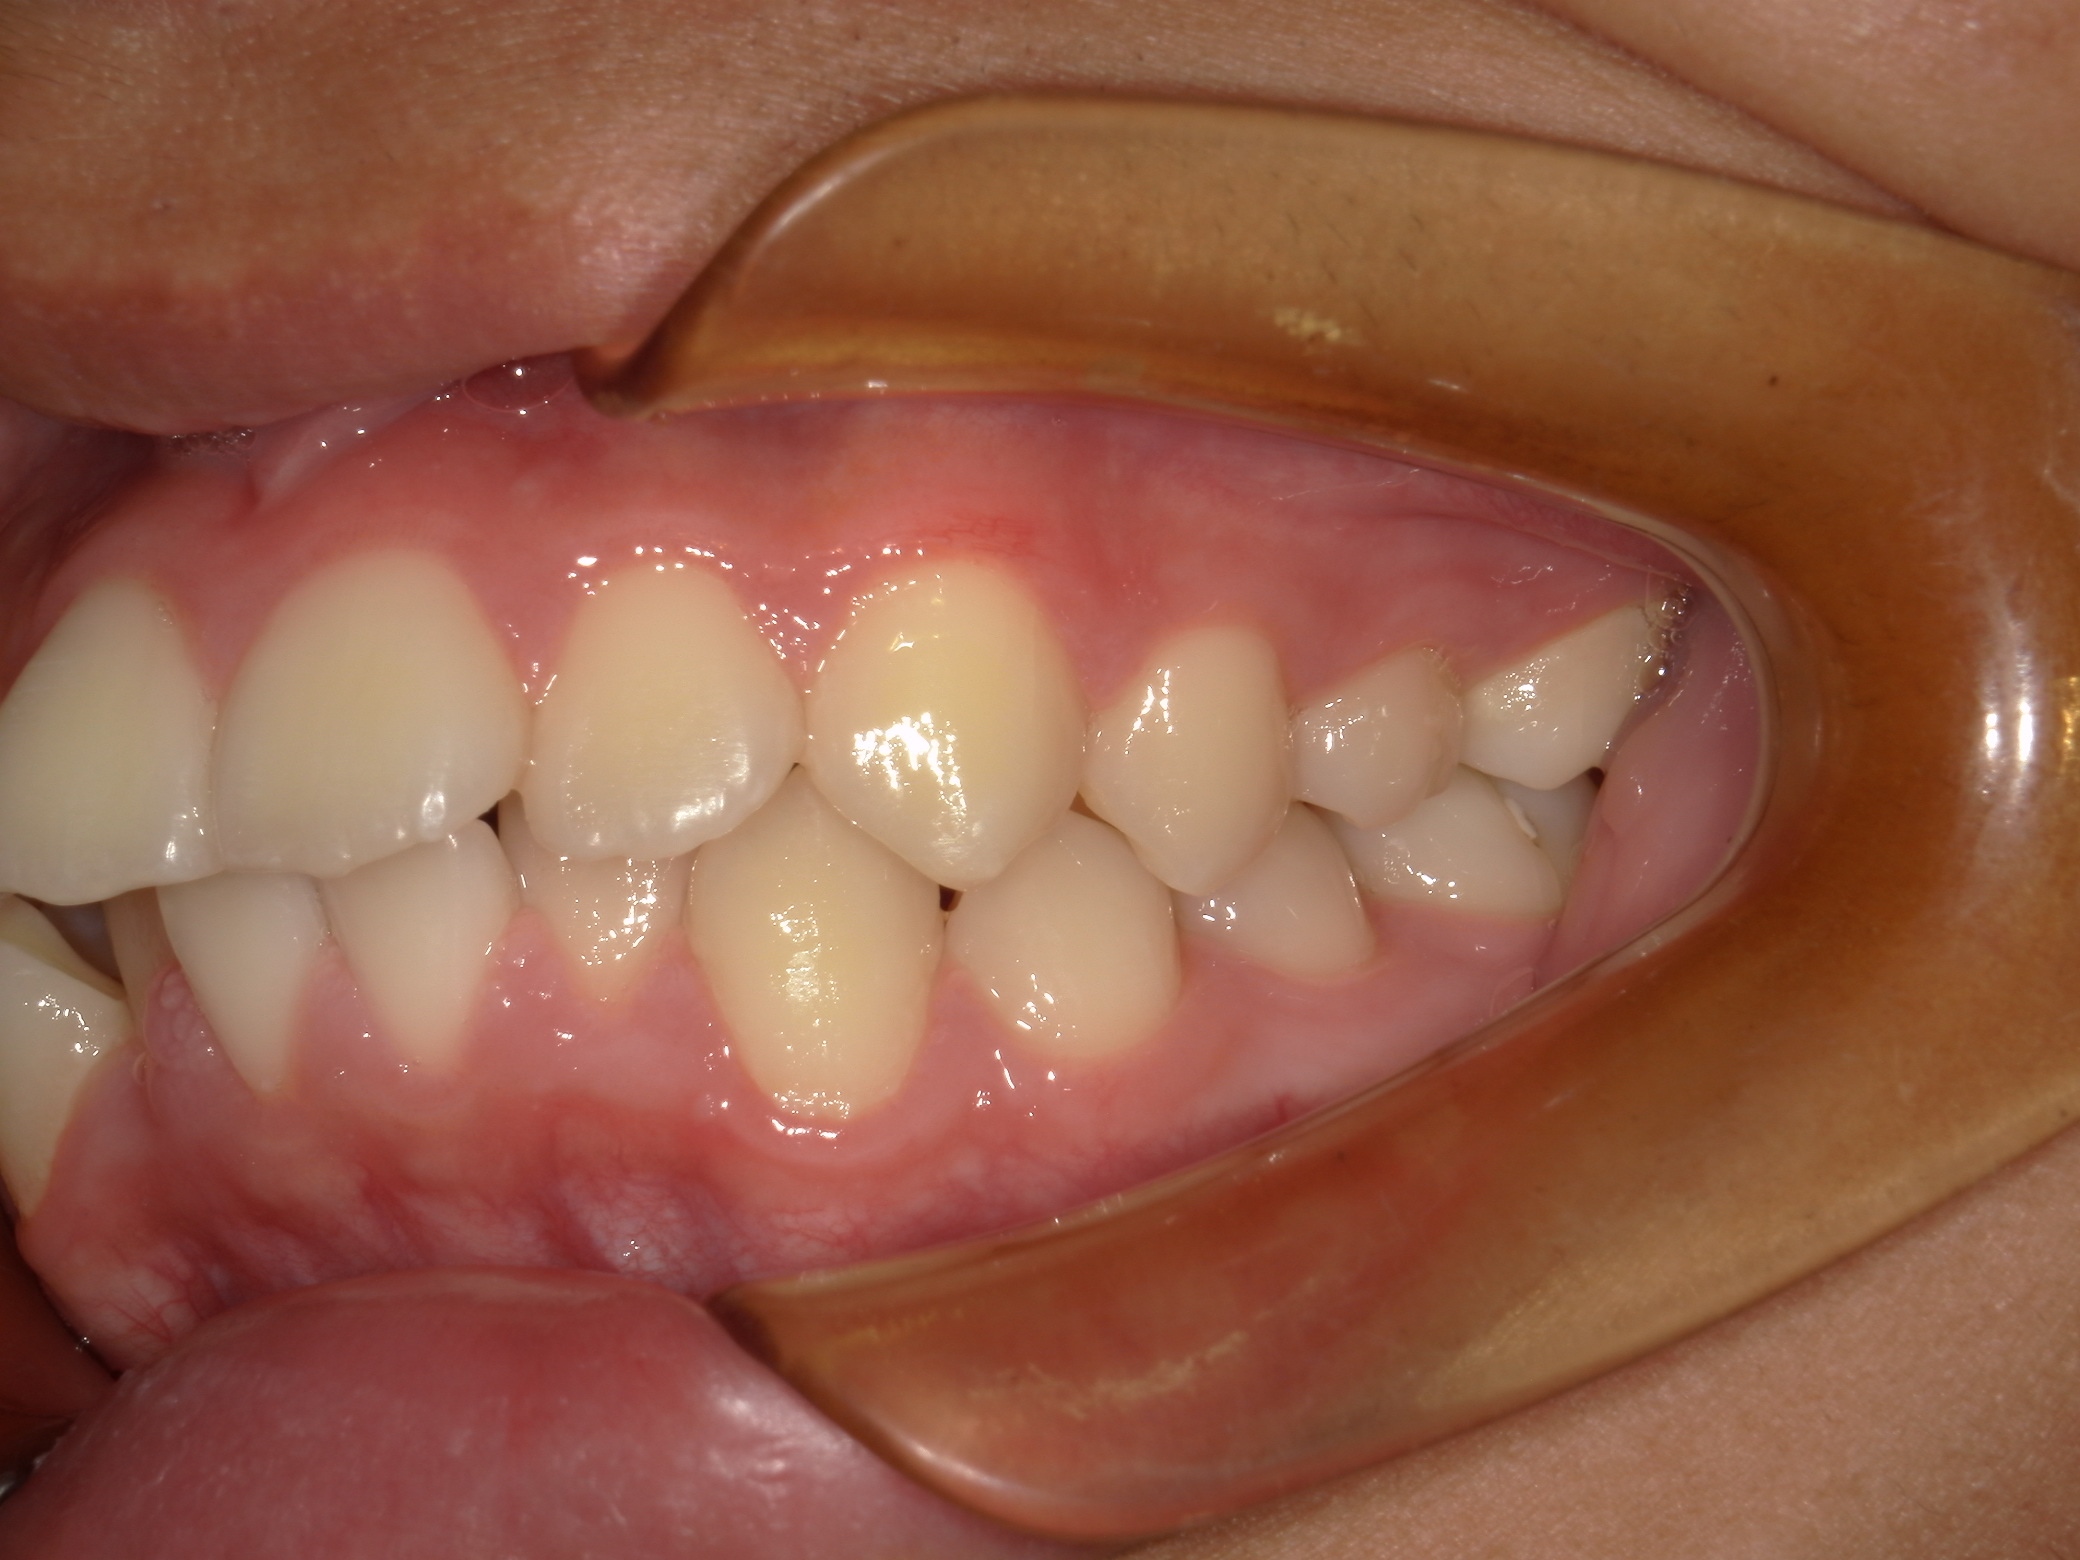

口内左

治療前

治療後